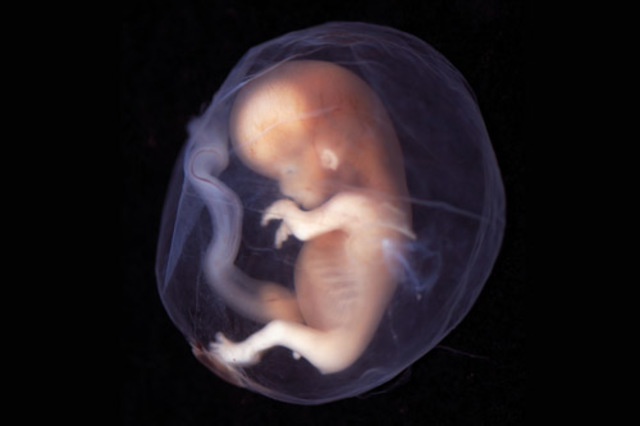

• 8 Semanas (Feto)

8 Semanas (Feto)

*El embrión pasa a llamarse feto

* El saco vitelino se marchita, y la placenta asume la función de alimentar y nutrir al feto.